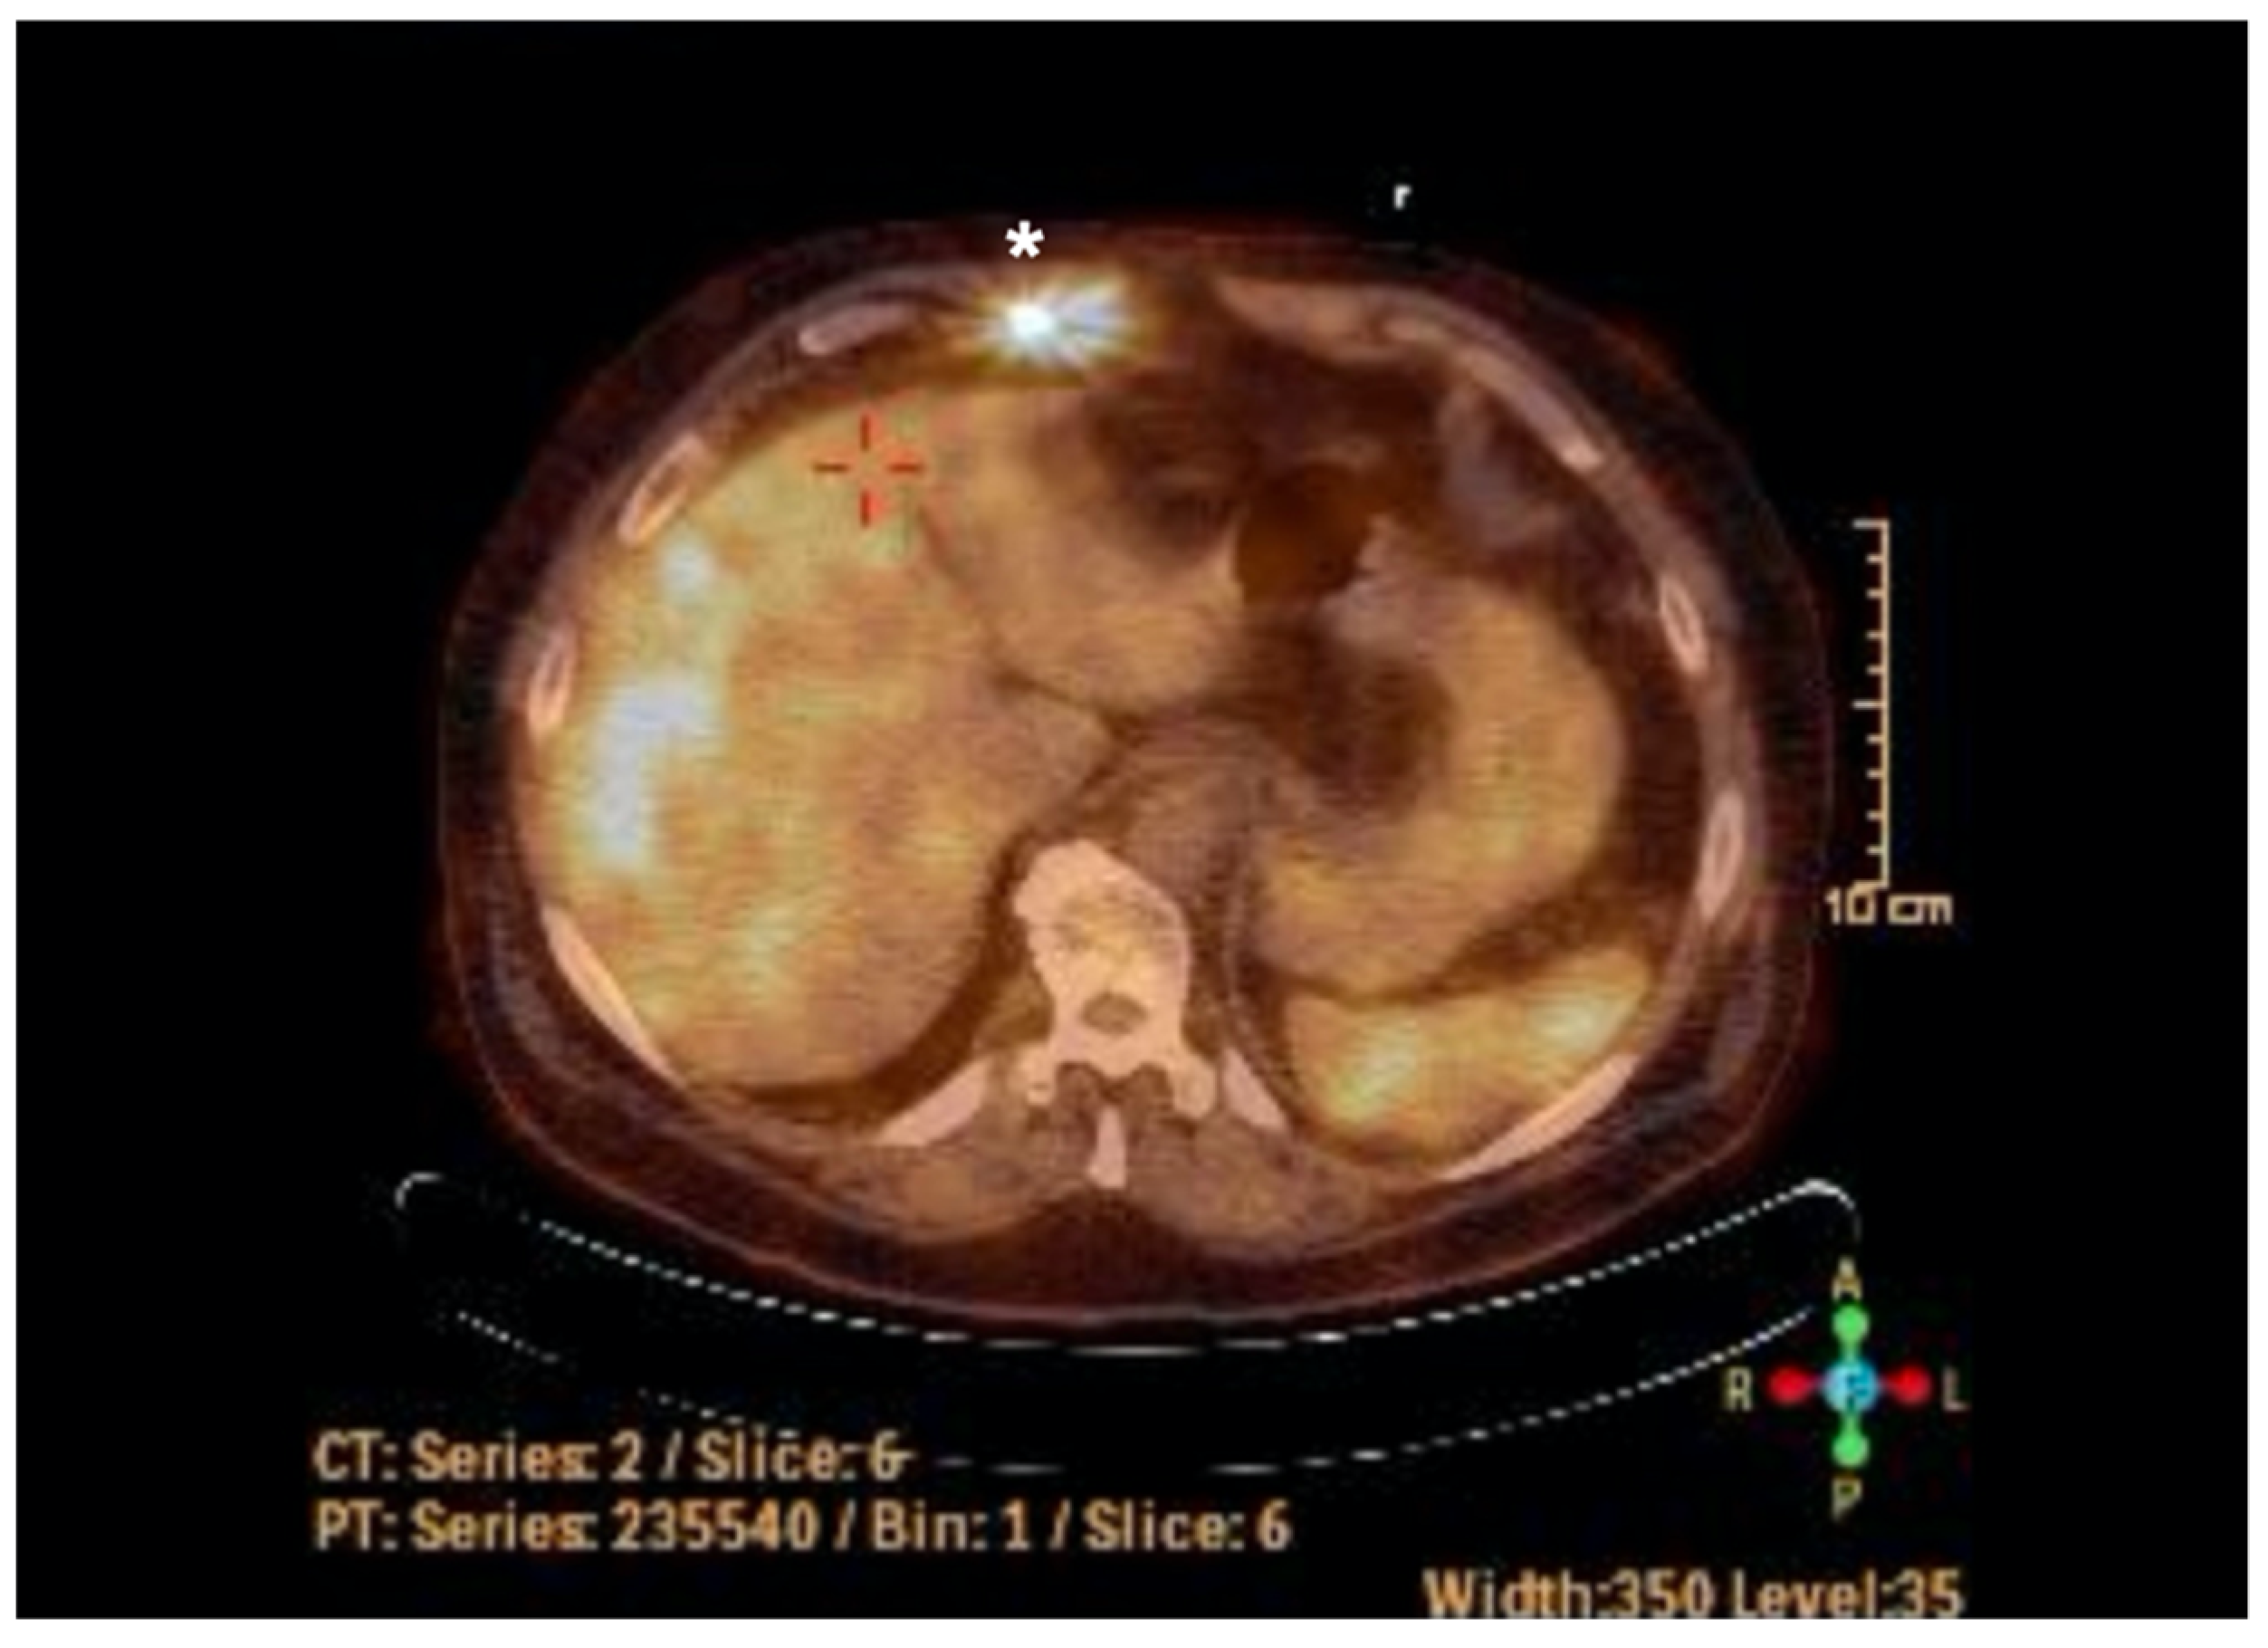

2. Case Report